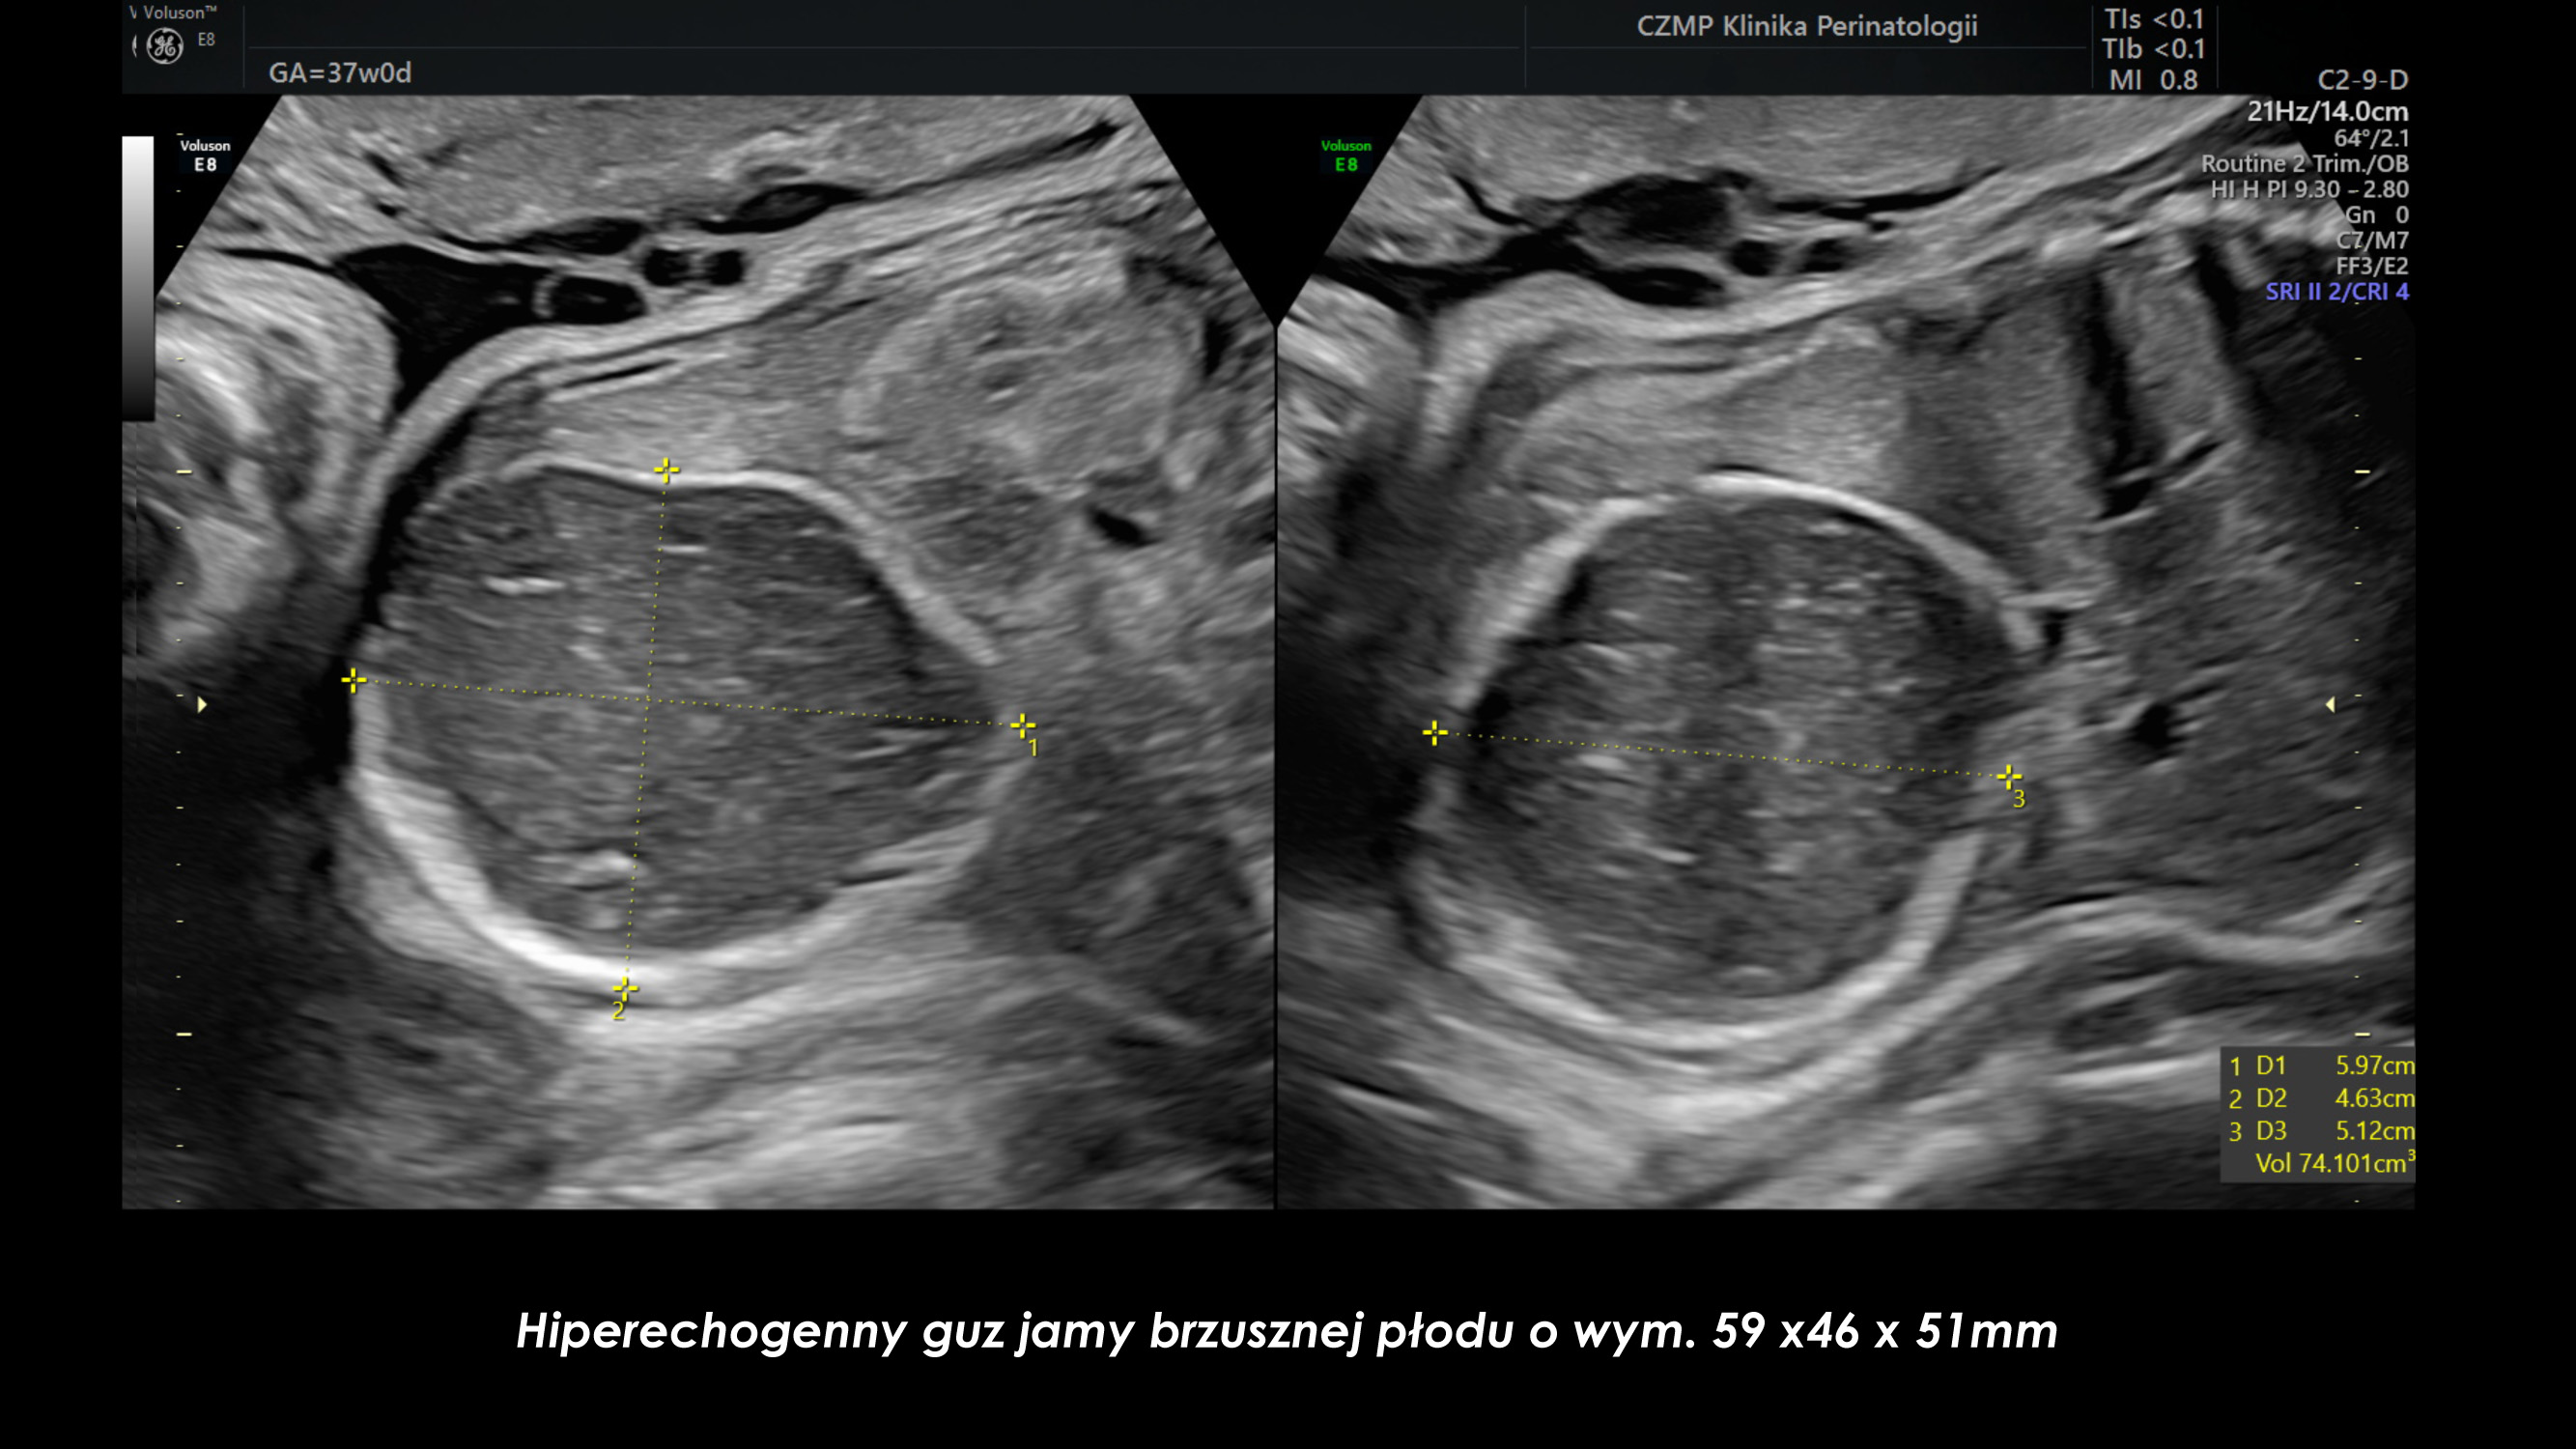

Nietypowy guz jamy brzusznej płodu